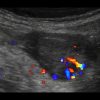

Mucocele ruột thừa

» Thông tin: Nam giới – 71 tuổi.

» Lâm sàng: Đau hố chậu phải mạn tính.